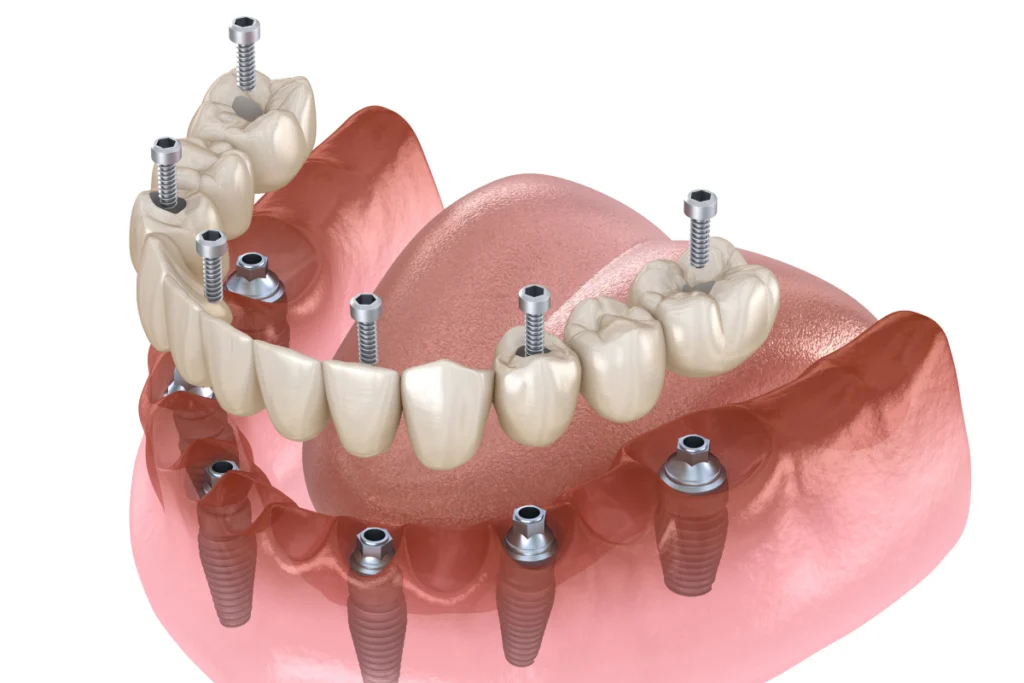

Implant complet : pour la réhabilitation totale d’une mâchoire

Dans certains cas, la réhabilitation complète de la mâchoire est nécessaire. Les implants sont utilisés pour soutenir une prothèse complète, remplaçant l’ensemble des dents d’une mâchoire. Cette solution permet de restaurer la fonction masticatoire et l’esthétique du sourire.

L’implant complet est une option idéale pour les patients ayant perdu toutes leurs dents. Il offre une stabilité et un confort supérieurs par rapport aux prothèses traditionnelles. Cette solution permet de conserver l’os de la mâchoire et d’améliorer la qualité de vie du patient.

3. Mise en place de la prothèse

Une fois l’implant stabilisé, une empreinte est réalisée. La couronne ou la prothèse est ensuite fabriquée sur mesure. Elle est fixée sur l’implant afin de reconstituer la dent.

L’objectif est d’obtenir un résultat harmonieux, stable et fonctionnel.

Oui. Nous pouvons remplacer une dent, plusieurs dents ou stabiliser une prothèse complète à l’aide de plusieurs implants. La solution est définie après un bilan personnalisé.